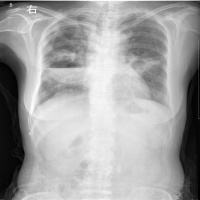

1X线检查 咯血患者均应做X线检查,胸部透视,胸部平片体层摄片,有必要时可做支气管造影协助诊断。 2CT检查 有助于发现细小的出血病灶。

X线检查X线检查在肺结核的诊断上有很高的价值,大致表现有:斑点结节状,密度较高边缘清楚的纤维包围的干酪灶;云雾状或片状,密度较淡,边缘完整密度不均匀的球形病灶;具有环形边界透亮葋的空洞形成。

X线检查一般患者X线平片上极少有征象。重度患者胸片显示一侧或双侧下肺纹理增粗,絮乱以及呈蜂窝壮阴影或见有小的液平面。支气管造影确定扩张的部位,范围形状并可决定治疗方案。

X线检查病变初期为片状浓密阴影,后渐向周围肺组织扩展,而且不受叶间胸膜限制脓腔形成后则内壁光滑,常有液平,脓腔周围有炎症浸润后期脓腔渐缩小,炎润渐消退,最后形成少许条索状阴影而痊愈 一般根据急性发病史临床表现、X线检查,痰细菌学检查和诊断断性治疗诊断不困难。